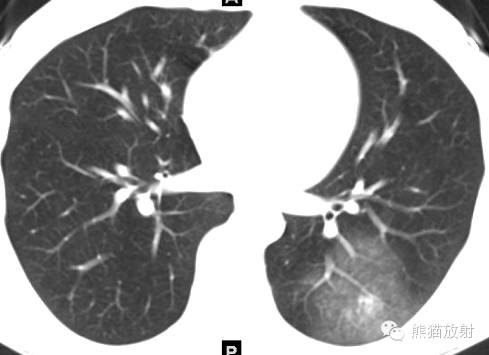

女,19岁,每次来月经时咯血。

CT诊断:结合病史,考虑左下肺子宫内膜异位症(渗出型),建议月经间期复查。

诸病灶分别如下图中圆圈所示: